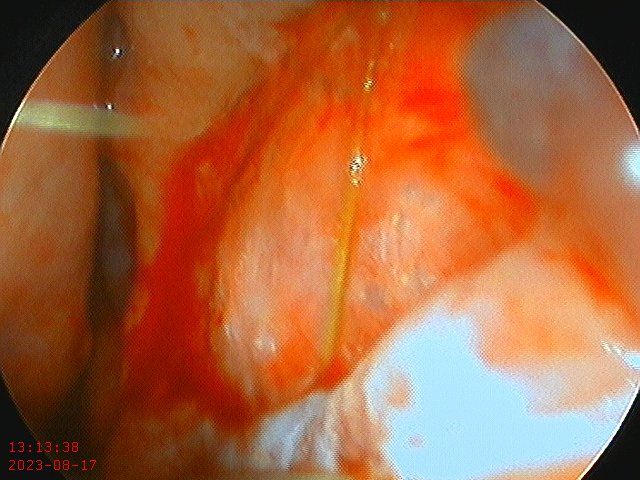

Perforation prior to repair

Temporalis fascia/PDS plate construct

Fascia/Pds plate within the perforation closing a large, 2.5 cm perforation.